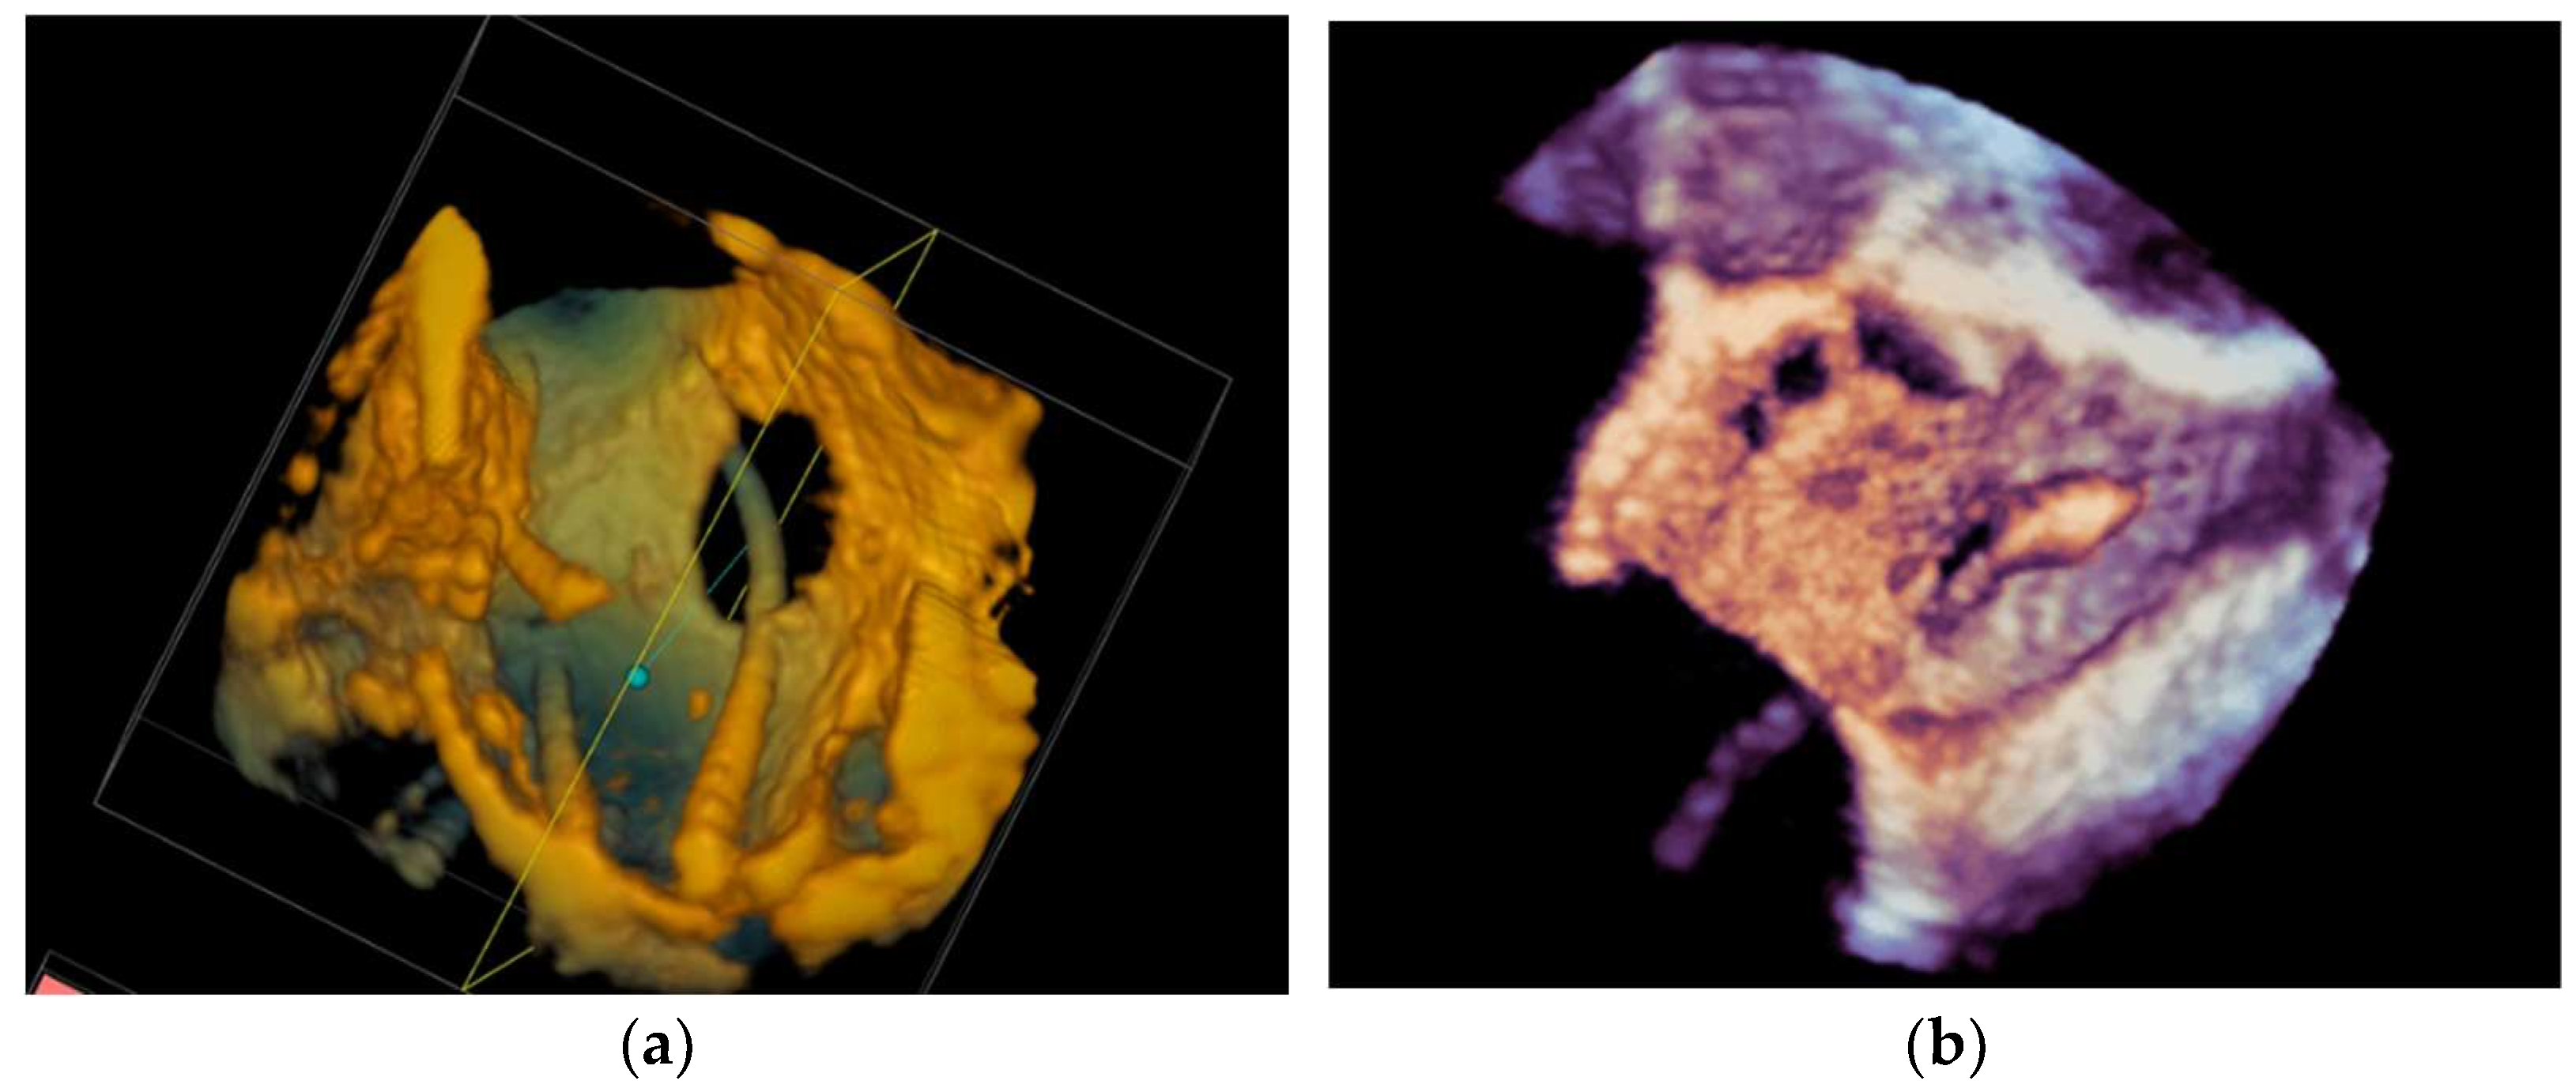

4.2.5. Paravalvular Leak Closure